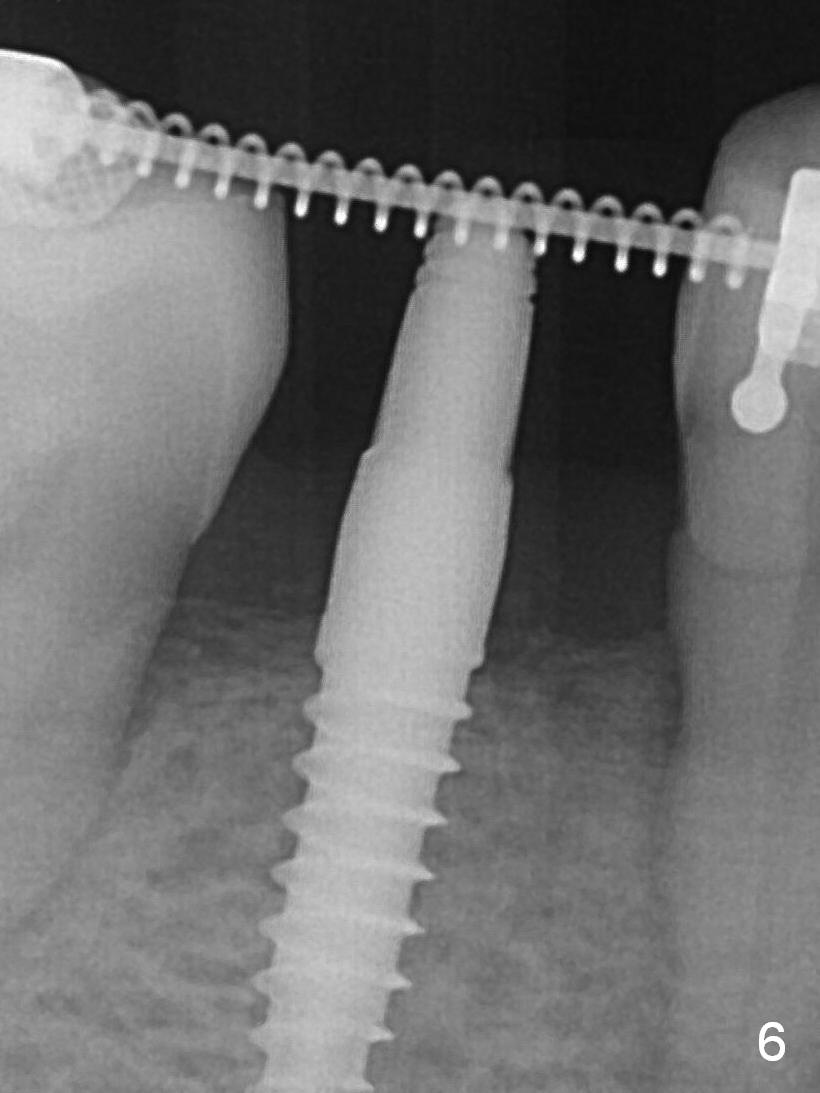

A 3x12(2) mm 1-piece implant is placed (Fig.4) with insertion torque > 40 Ncm. There is no bone loss 3 months postop (Fig.6), 3.5 months post cementation (Fig.9) or 3 years 7 months post cementation (Fig.12).